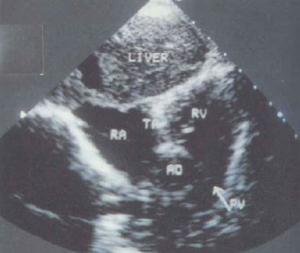

(5)M型超声心动图显示三尖瓣双峰曲线消失,四腔切面检查未能见到三尖瓣回声反射,房间隔回声中断,并有心室间隔上部回声中断。超声心动图和多普勒检查并可见到血流自右房至左心房再进入左室。二尖瓣活动幅度增大,右房、左房、左室腔均增大,右心室小或消失。